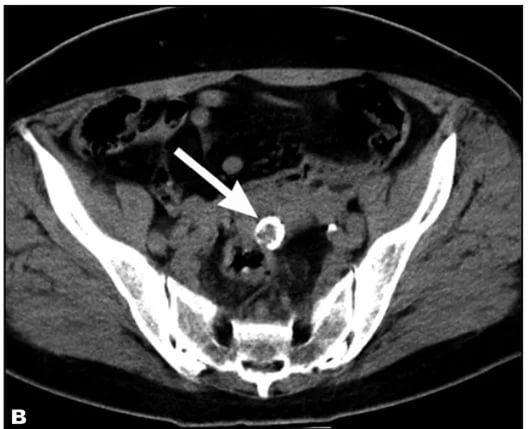

| Диагностика | УЗИ, КТ, МРТ. | Визуализация кальцификатов в миоме на изображениях. |

Для диагностики данного типа новообразований используются те же методы, что и для обычных опухолей. Тем не менее, ультразвуковое исследование может столкнуться с определенными трудностями. Кальцинированные опухоли иногда сложно идентифицировать на УЗИ, особенно если они небольшие.

Более четкие результаты можно получить только при наличии узлов диаметром от 8 мм, так как они кальцинируются довольно редко. Обычно наличие таких новообразований на УЗИ определяется по гиперэхогенным включениям с акустическим эффектом.